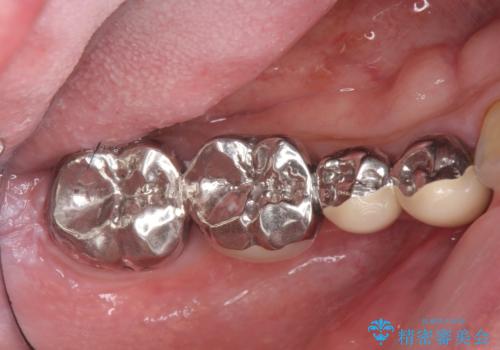

銀歯だらけの口の中を改善したい

- 銀歯だらけの口の中に嫌気がさし、改善を求めて来院されました。

設計に無理のある長期的に良好な状態が保てるとは思えないブリッジを除去し、インプラントを用いた補綴計画を立てます。